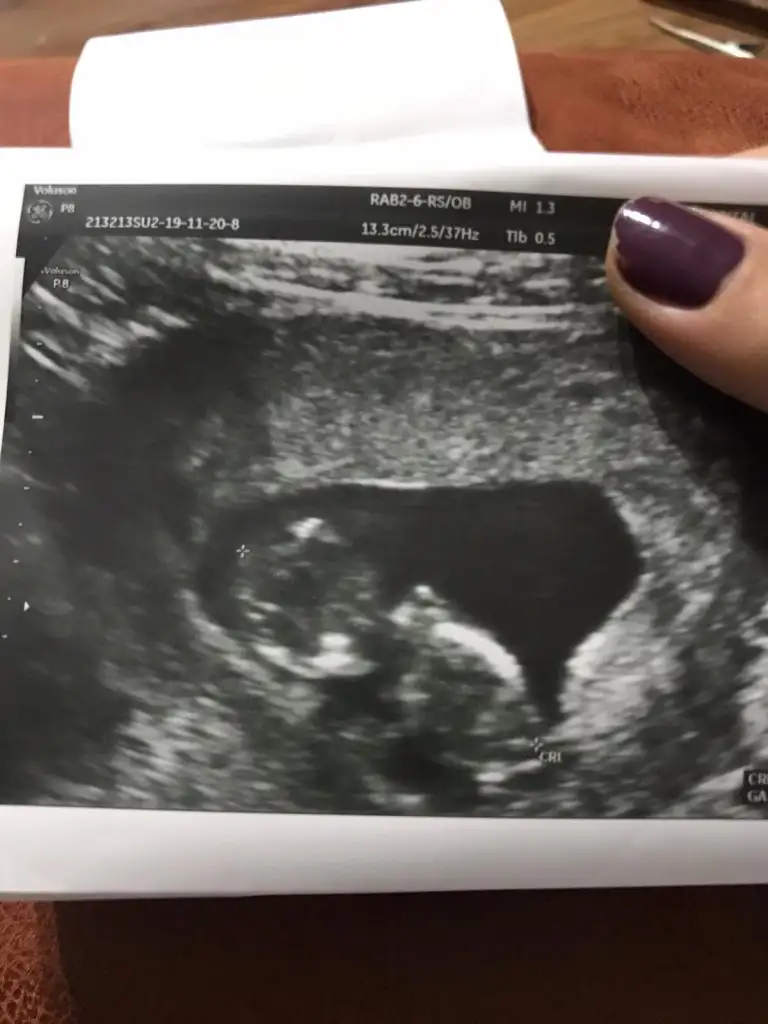

Buna da bakarmısınız 11+5 arkadaşın

13. Haftalık 11 ve 12. Haftalıkken doktora gitmedik kontrolümüz 13. Haftaya denk geldi o yüzden bu başka da var ama net değil ki atayım ben yine deerkek gibi başka usg var kaç haftalık